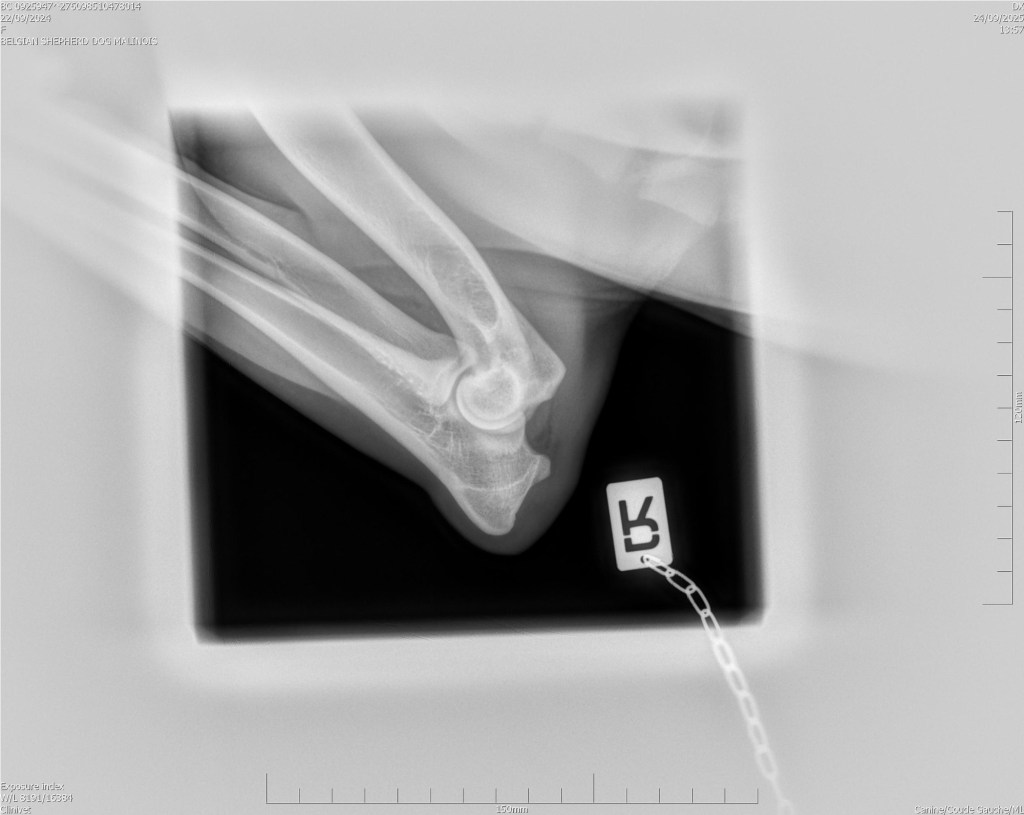

Hips 2/3

Elbows 0/0